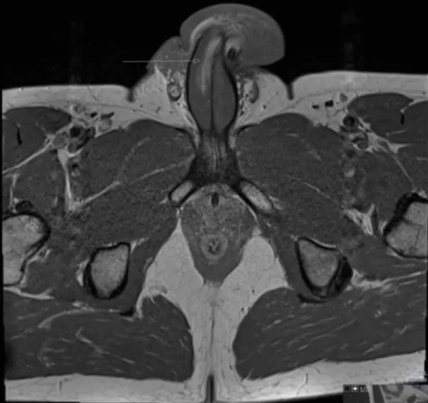

МРТ зафиксировала вертикальный разрыв длиной три сантиметра с правой стороны члена. Ученые не смогли сфотографировать гениталии из-за антиковидных ограничений, но приложили к работе снимок томографа.